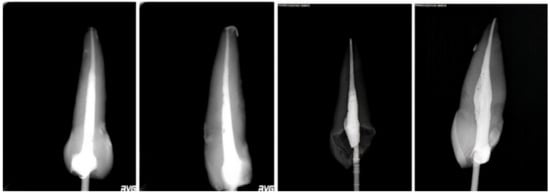

- The GuttaCore System shows a better filling at the level of the apical third with a percentage of voids equal to 5%. The percentage of voids increases at the level of the coronal third and middle third of the root canal equal to: 12.1% coronal voids; 20.5% in the middle portion 2; 17.25% in the middle portion 1 (Table 1).

- On the contrary, because of its greater fluidity, the GuttaFlow System allows a better filling at the coronal level and in the middle third, with a percentage of voids equal to 1.6% coronal; 6.8% in the middle portion 2; 12.5% in the middle portion 1; on the contrary, the percentage of voids at the apical interface increased significantly, equal to 26% (Table 1).

| Coronal | 49.86 | 24.92 | 1.6 | Coronal | 364.87 | 182.43 | 12.1 |

| Middle 2 | 130.84 | 65.42 | 6.8 | Middle 2 | 390.27 | 195.13 | 20.5 |

| Middle 1 | 200.76 | 100.38 | 12.5 | Middle 1 | 274.19 | 137.09 | 17.25 |

| Apical | 321.27 | 160.06 | 26 | Apical | 60.05 | 30.02 | 5 |